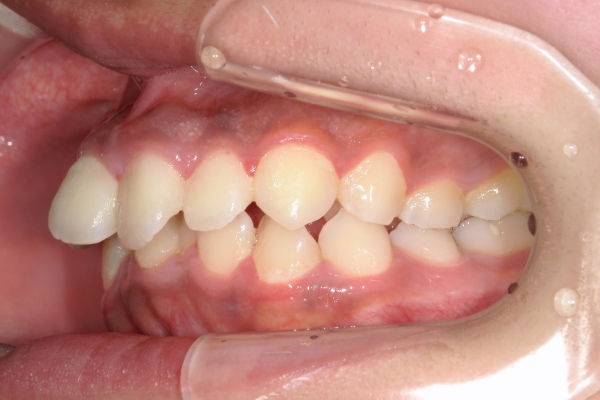

BEFORE

治療前

AFTER

治療後

上顎前歯が1cm近く前方に出ており、叢生を改善しつつ前歯を大きく引っ込めるために上下顎小臼歯の抜歯が必要と診断しました。治療後は、主訴であった前歯の突出と奥歯の噛み合わせのずれが改善され、上下の咬合関係が安定しました。